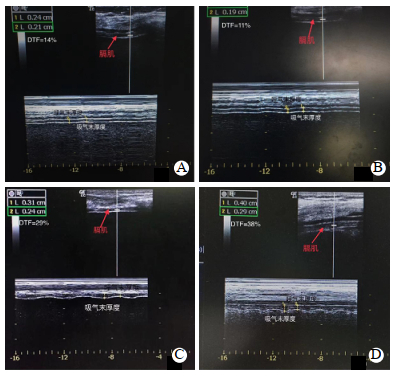

1.2.4 床旁超声评估膈肌功能脓毒症和感染性休克患者入ICU第1、3、7天,术后对照组入ICU第1天由同一位超声科医师使用美国GE超声诊断仪(型号为LOGIQ C5/C5 PRO, )测量。本研究统一测量右侧膈肌,测量时床头抬高30°,呼吸机CPAP模式,PEEP 5 cmH2O(1 cmH2O=0.098 kPa)[6]。测量具体方法参照[7-8](如图 1、2)。测量同一呼吸周期内膈肌移动度(diaphragmatic excursion,DE)、吸气末膈肌厚度(DTei)及呼气末膈肌厚度(DTee),测量3次取平均值。DE < 10 mm或出现膈肌矛盾运动诊断膈肌功能障碍[9]。计算膈肌增厚分数(DTF)、膈肌浅快呼吸指数(D-RSBI)及膈肌增厚浅快呼吸指数(DT-RSBI),具体公式如下:DTF =(DTei−DTee)/DTee×100%,D-RSBI=呼吸频率(RR)/DE,DT-RSBI=RR/DTF。McCool等[10]提出DTee≤2 mm,DTF < 20%提示膈肌功能障碍。

| A:感染性休克患者;B:脓毒症患者;C:术后患者;D:健康志愿者 图 1 膈肌移动度 Fig 1 Diaphragmatic excursion |

| A:感染性休克患者;B:脓毒症患者;C:术后患者;D:健康志愿者 图 2 膈肌厚度 Fig 2 Diaphragmatic thickness |